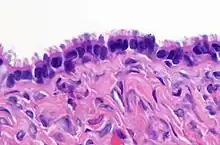

| Surface epithelial-stromal tumor | Serous tumor | 25% | 18.5% | Benign serous tumors of the right ovarian cyst are thinwalled unilocular cysts that are lined by ciliated pseudostratified cuboidal or columnar epithelium.[21] | ![]() |